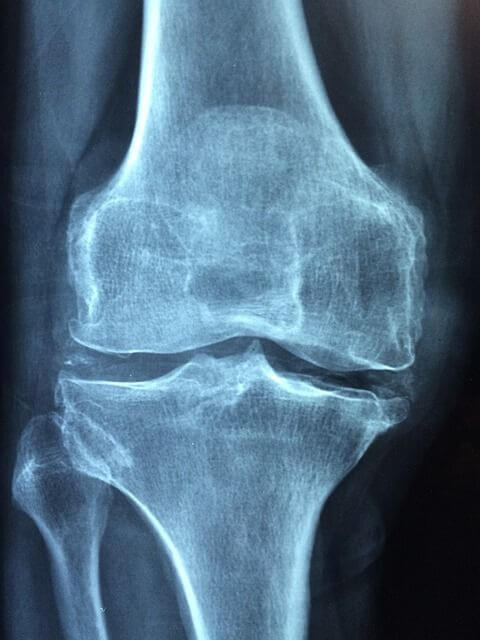

류마티스 관절염의 병리학적 특징은 활막의 염증과 증식, 국소적인 골미란과 관절연골이 얇아지는 것입니다. 만성적인 염증인 활막 표면과 판누스(pannus)를 형성합니다. 지속적으로 활성화된 류마티스 관절염은 관절연골, 뼈를 파괴하고, 이로 인한 기능 장애를 일으킨다. 전신 질환으로, 피로, 피하결절, 폐 침범, 삼막염, 말초 신경병증, 혈관염, 혈액학적 이상 등 다양한 관절 외 증상이 발현됩니다.

류마티스 관절염의 증상은 먼저 손에서 나타납니다. 손가락손허리뼈와 몸 쪽손가락관절에 침범하지만, 질병 후기에는 먼쪽 손가락관절에도 침범될 수 있습니다. 류마티스관절염이 진행되면서, 손이 변형이 일어나서 손가락손허리뼈는 척골편위가 발생하고, 백조목 변형 및 단추구멍 변형이 나타날 수 있다. 또한, 건초염 혹은 건막의 결절에 의한 방아쇠 손가락이 유발될 수 있고, 심한 경우 건파열이 생기며 4.5번째 수지의 신전부에서 가장 호발합니다. 류마티스관절염의 팔꿈치관절의 활막염은 류마티스환자의 50%에서 관찰된다. 팔꿈치에서의 구축도 잘 오지만, 환자는 잘 모를 수 있으니 주의가 필요합니다.